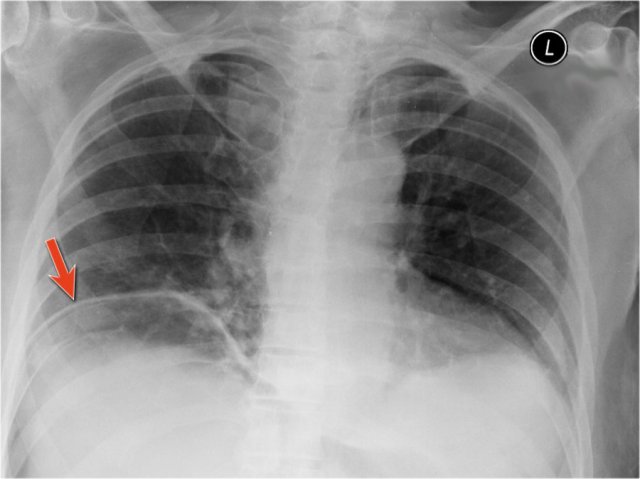

An important mediastinal-lung interface to look for is the azygoesophageal line or recess (arrow).

Azygo-esophageal recess

The azygo-esophageal recess is the region inferior to the level of the azygos vein arch in which the right lung forms an interface with the mediastinum between the heart anteriorly and vertebral column posteriorly.

It is bordered on the left side by the esophagus.

Deviation of the azygoesophageal line is caused by:

- Hiatal hernia

- Esophageal disease

- Left atrial enlargement

- Subcarinal lymphadenopathy

- Bronchogenic cyst

Notice the deviation of the azygoesophageal line on the PA-film.

It is caused by a hiatal hernia.

The arrow point to the barium contrast within the hiatal hernia.